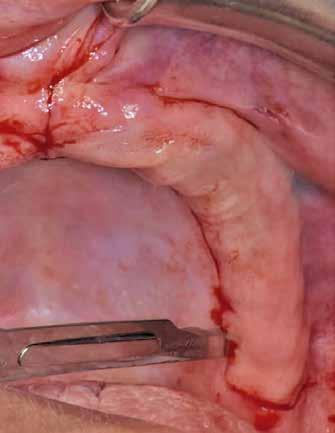

A fogak eltávolítása és az alveoláris csont megőrzésének és regenerációjának segítése céljából elvégzett augmentáció altatásban történt. Óvatos, atraumatikus extrakciót követően eltávolítottuk a parodontális és periapikális gyulladásos folyamatok eredményeként jelen lévő sarjszövetet. A bukkális csontfal hiánya és a tervezett vertikális augmentáció miatt indokolt membrántechnika megfelelő kivitelezése céljából a felső állcsonton mukoperioszteális lebenyt képeztünk (3–4. ábra). Az alveolus prezervációt Sticky Tooth, PRF és titánerősítésű teflon (PTFE-Ti) membránok segítségével végeztük el, a J. Choukroun által megadott vérvételi és centrifugálási protokoll (28) elveinek betartásával: kizárólag Process for PRF Duo Quattro System eszközöket, centrifugát, vérvételi egységet és csöveket, a membránok előállításához PRF Boxot használtunk. Az A-PRF és S-PRF csöveket a PomPac eljárásnak megfelelően 4 Celsius-fokra előhűtöttük. Az eltávolított fogak makroszkópos tisztítását és darabolását nagy fordulattal (300 000 RPM) fogászati turbinába helyezett gyémántfúróval végeztük, majd Tooth Transformer™ berendezéssel, annak gyári reagens rendszerével kezelt őrleményt nyertünk. A Sticky Tooth készítmény előállítása a PRF készítmény és az őrlemény

60/40 arányú keverésével történt (5–7. ábra), A-PRF és A-PRF/S-PRF membránokat készítettünk (8. ábra). Az alveólusokat a grafttal feltöltöttük, a felső front régióban vertikális augmentációt végeztünk a tervezett alveoláris csontmagasság elérésének céljából (9–10. ábra). A vertikális augmentáció támogatására titán mikrocsavarokkal rögzített, titánerősítésű teflonmembránokat alkalmaztunk, amelyekre egy rétegben A-PRF membránokat, és egy rétegben A-PRF/S-PRF membránokat helyeztünk. Az alsó állcsont esetében vertikális augmentáció nem volt szükséges, célunk az alveoláris kemény- és lágyszöveti struktúrák prezervációja volt, a graftot csak PRF memb-

ránokkal fedtük. A PRF membránok külön rögzítést egyik állcsont esetében sem kaptak (11–12. ábra). A mukogingivális lebenyt – annak megnyújtása nélkül – a helyére fektettük és varratokkal rögzítettük, per primam sebzárást nem végeztünk. A varratokat 2 hét után távolítottuk el, a varratszedésig a sebgyógyulás támogatására per os 1000 mg/nap C- és 12 000 NE/nap D-vitamint adtunk (28).